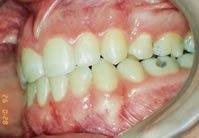

Antes

DepoisTratamento executado sem extrações. Tempo de tratamento de 20 meses. Em nossa clínica abolimos o uso do extra-bucal. Com técnicas mais recentes, temos conseguido resultados melhores e em menos tempo.